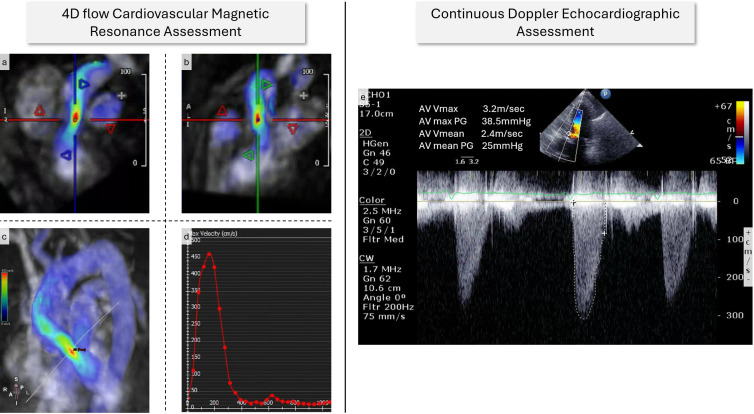

Aims: Four-dimensional flow cardiovascular MRI (4D flow CMR) has emerged as a promising technique for assessing aortic stenosis (AS). This study aimed to evaluate the agreement between 4D flow CMR and transthoracic echocardiography (TTE) in estimating peak aortic valve (AV) velocities (VPeak), grading AS severity and predicting AV intervention in a real-world setting.

Methods: Participants from the PREFER-CMR registry who had consecutive TTE and 4D flow CMR were included. AS severity was graded using established protocols using three echocardiographic parameters (VPeak, AV area and mean pressure gradient) and CMR-derived VPeak.

Results: The study recruited 30 patients (mean age 75.4 years, 67% male), with 17 undergoing AV intervention. Continuous wave Doppler (CWD) VPeak (3.4 vs 2.6 m/s, p=0.0025) and 4D flow VPeak (4.2 vs 2.7 m/s, p<0.0001) were significantly higher in patients going for AV intervention. VPeak by CWD was significantly lower to 4D flow with a bias of -0.5 (p=0.01) and a correlation of (R=0.55, p=0.002). The Cox-regression analysis reveals that 4D flow VPeak significantly predicts AV intervention (HR=2.51, p<0.01), while CWD VPeak (HR=0.54, p=0.76) shows no significant association; overall model fit is significant (χ²=9.5, p=0.02).

Conclusion: 4D flow CMR-derived VPeak assessment is superior to echocardiographic CWD assessment for predicting timing of AV intervention.